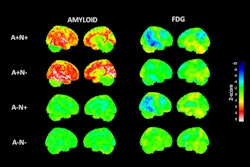

In other molecular imaging news, researchers from Madrid have reported that combining diagnostic information taken from an amyloid PET scan and an FDG-PET scan can predict the progression to Alzheimer’s disease in patients from mild cognitive impairment.